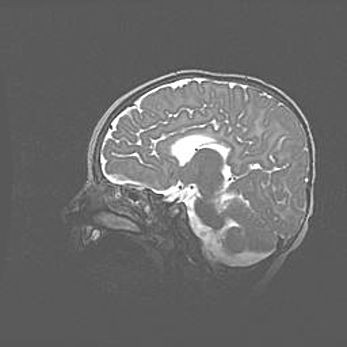

Церебральная ишемия II.

Возраст: 5 дней

Вес: 3400 г

Пол: женский

Окружность головы: 35 см

Срок гестации: 39 недель

Церебральная ишемия – это заболевание, характеризующееся недостаточностью (гипоксией) либо полным прекращением (аноксией) снабжения мозга кислородом по причине закупорки одного или нескольких сосудов. Это приводит к  что метаболическим расстройствам различной степени тяжести в тканях головного мозга, развитию коагуляционных некрозов и гибели нейронов.